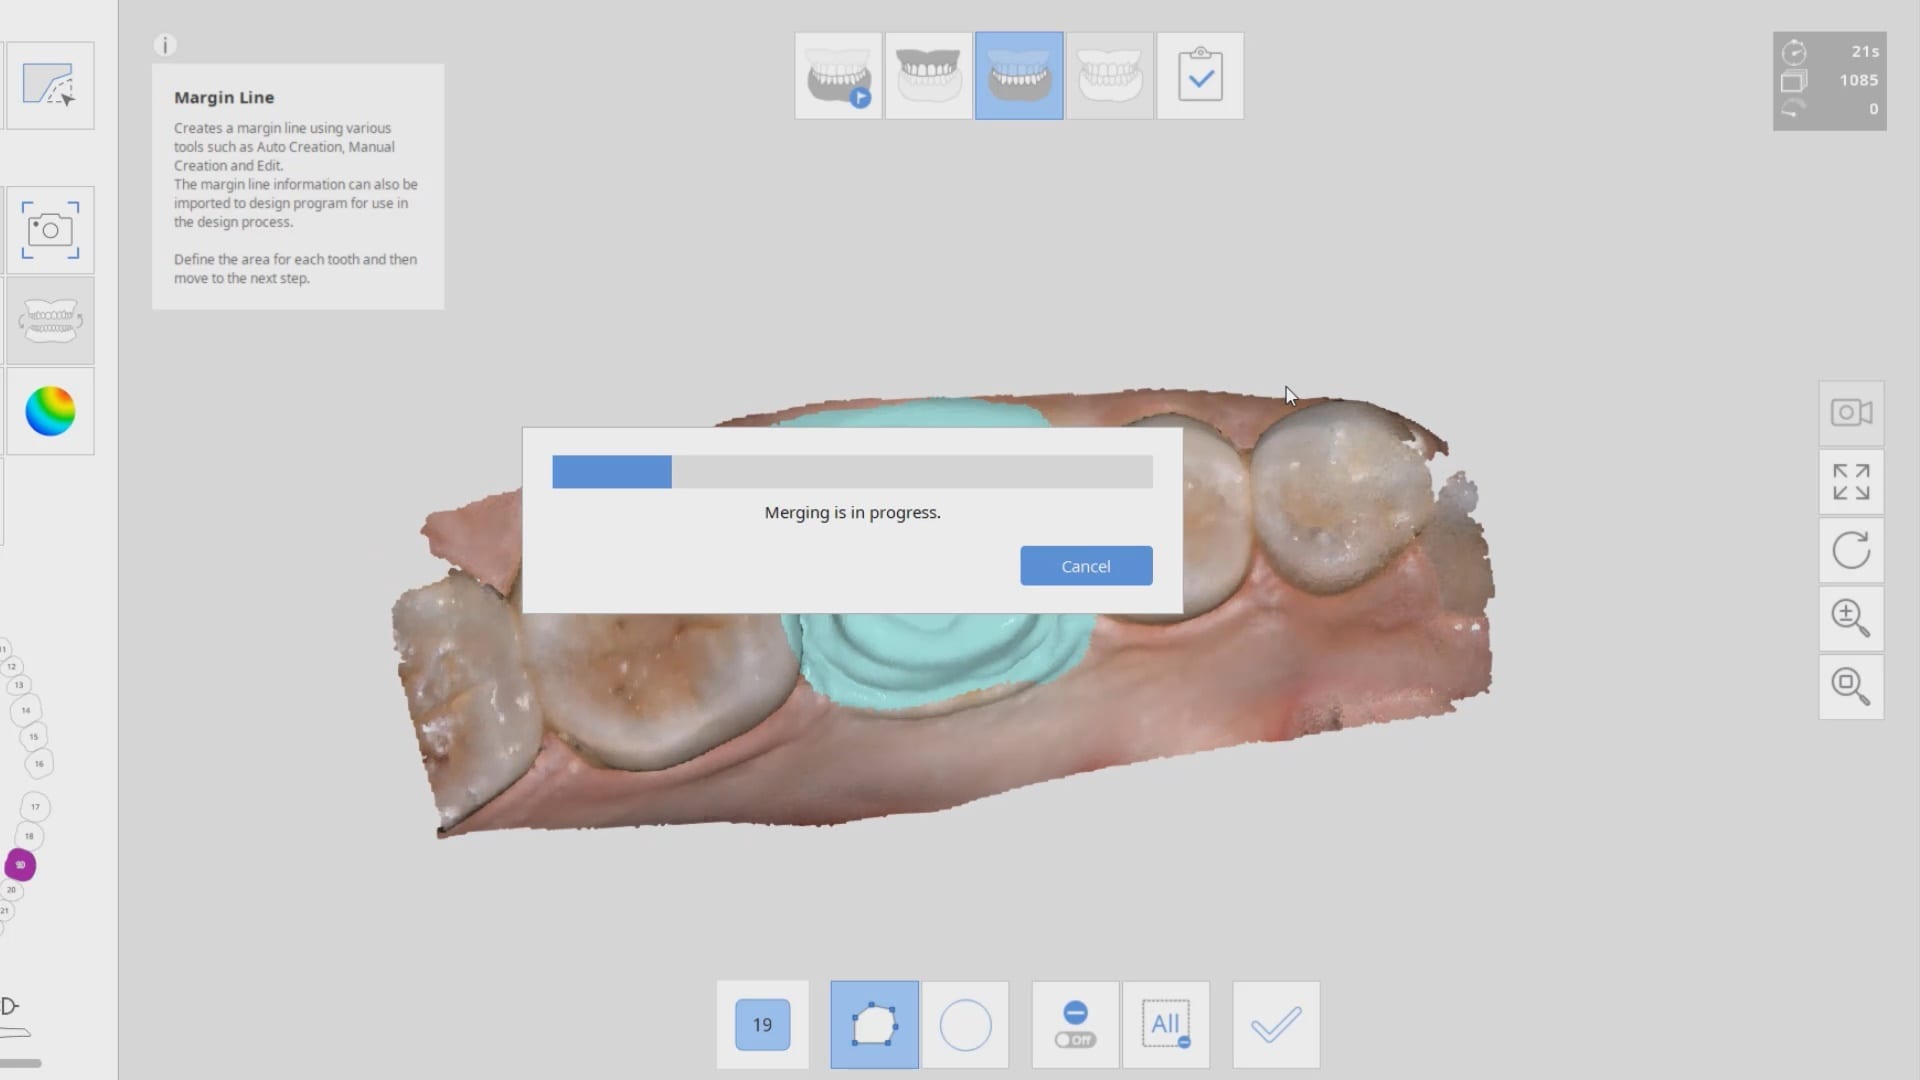

Second Molar Crown Replacement in Copy Mode

September 3, 2019In this case presentation, we feature a crown that needs to be replaced due to open margins and recurrent decay. With the Medit i500, after the patient is anesthetized and […]

In this case presentation, we feature a crown that needs to be replaced due to open margins and recurrent decay. With the Medit i500, after the patient is anesthetized and […]